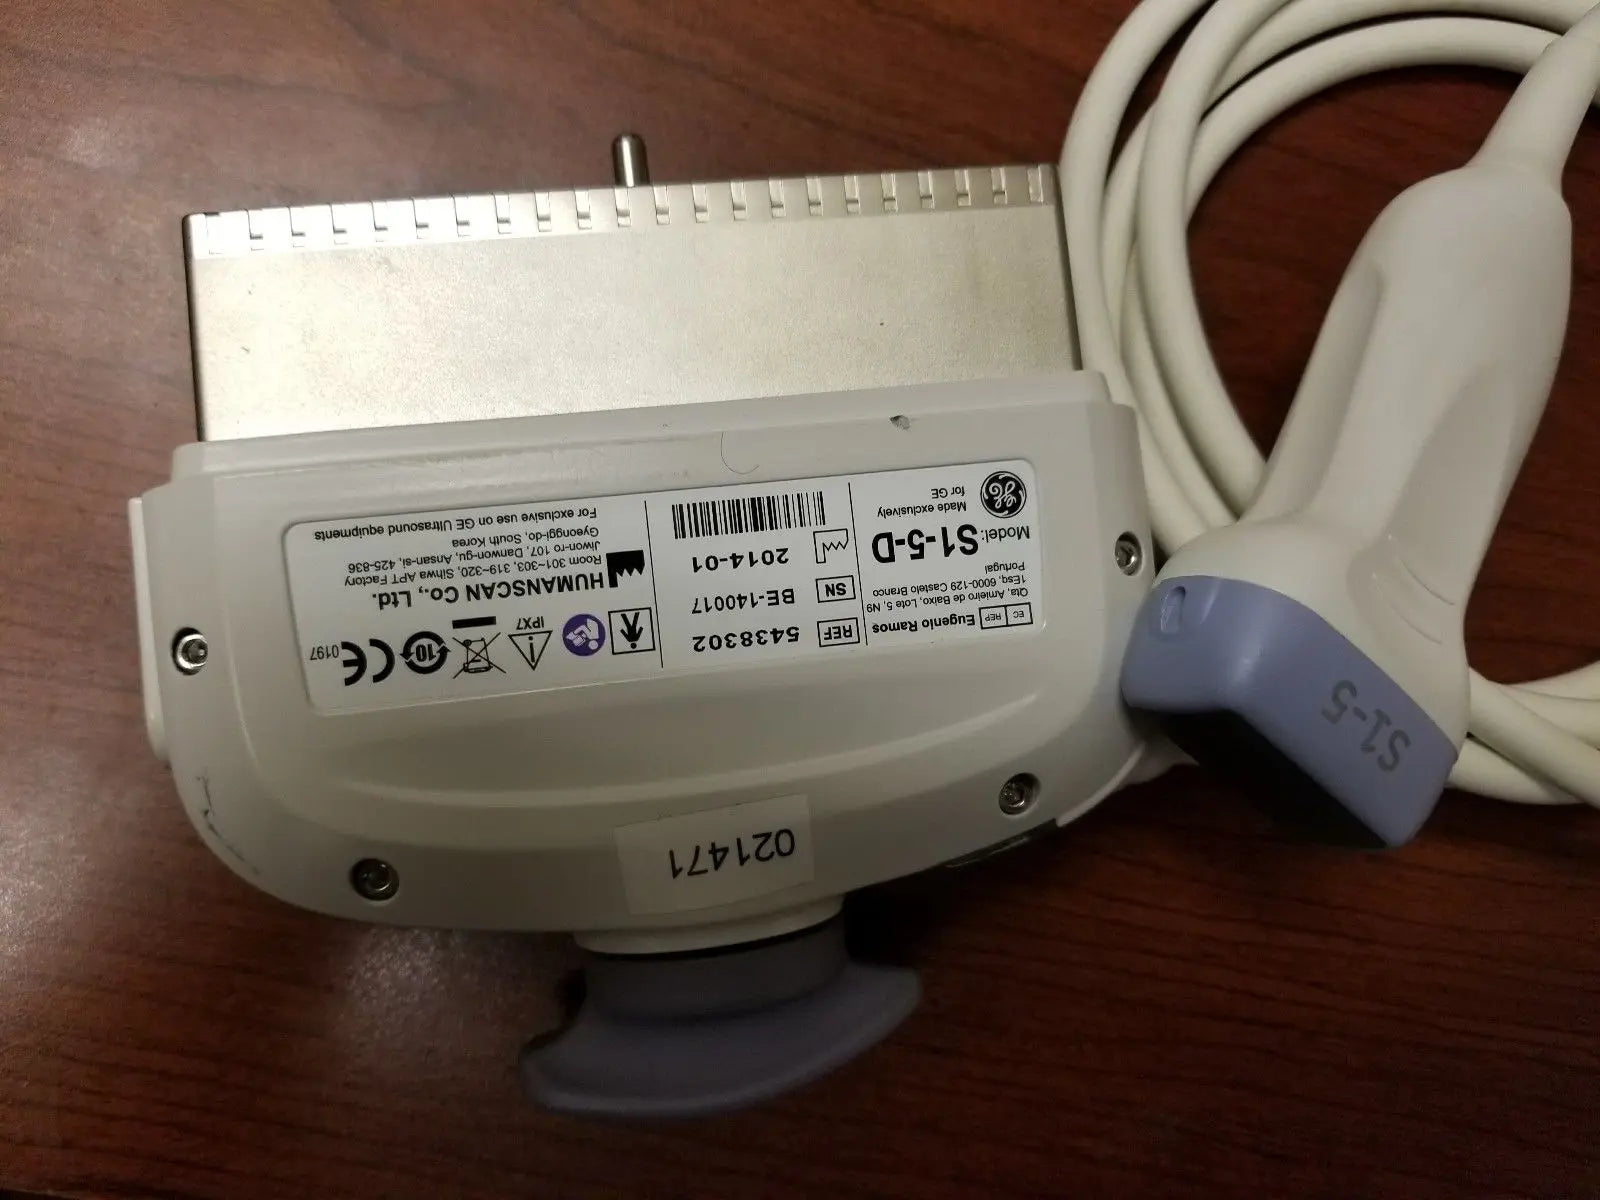

DIAGNOSTIC ULTRASOUND MACHINES FOR SALE

2017 GE IC9 -RS probe for GE Ultrasound

Sale price$ 8,395.14